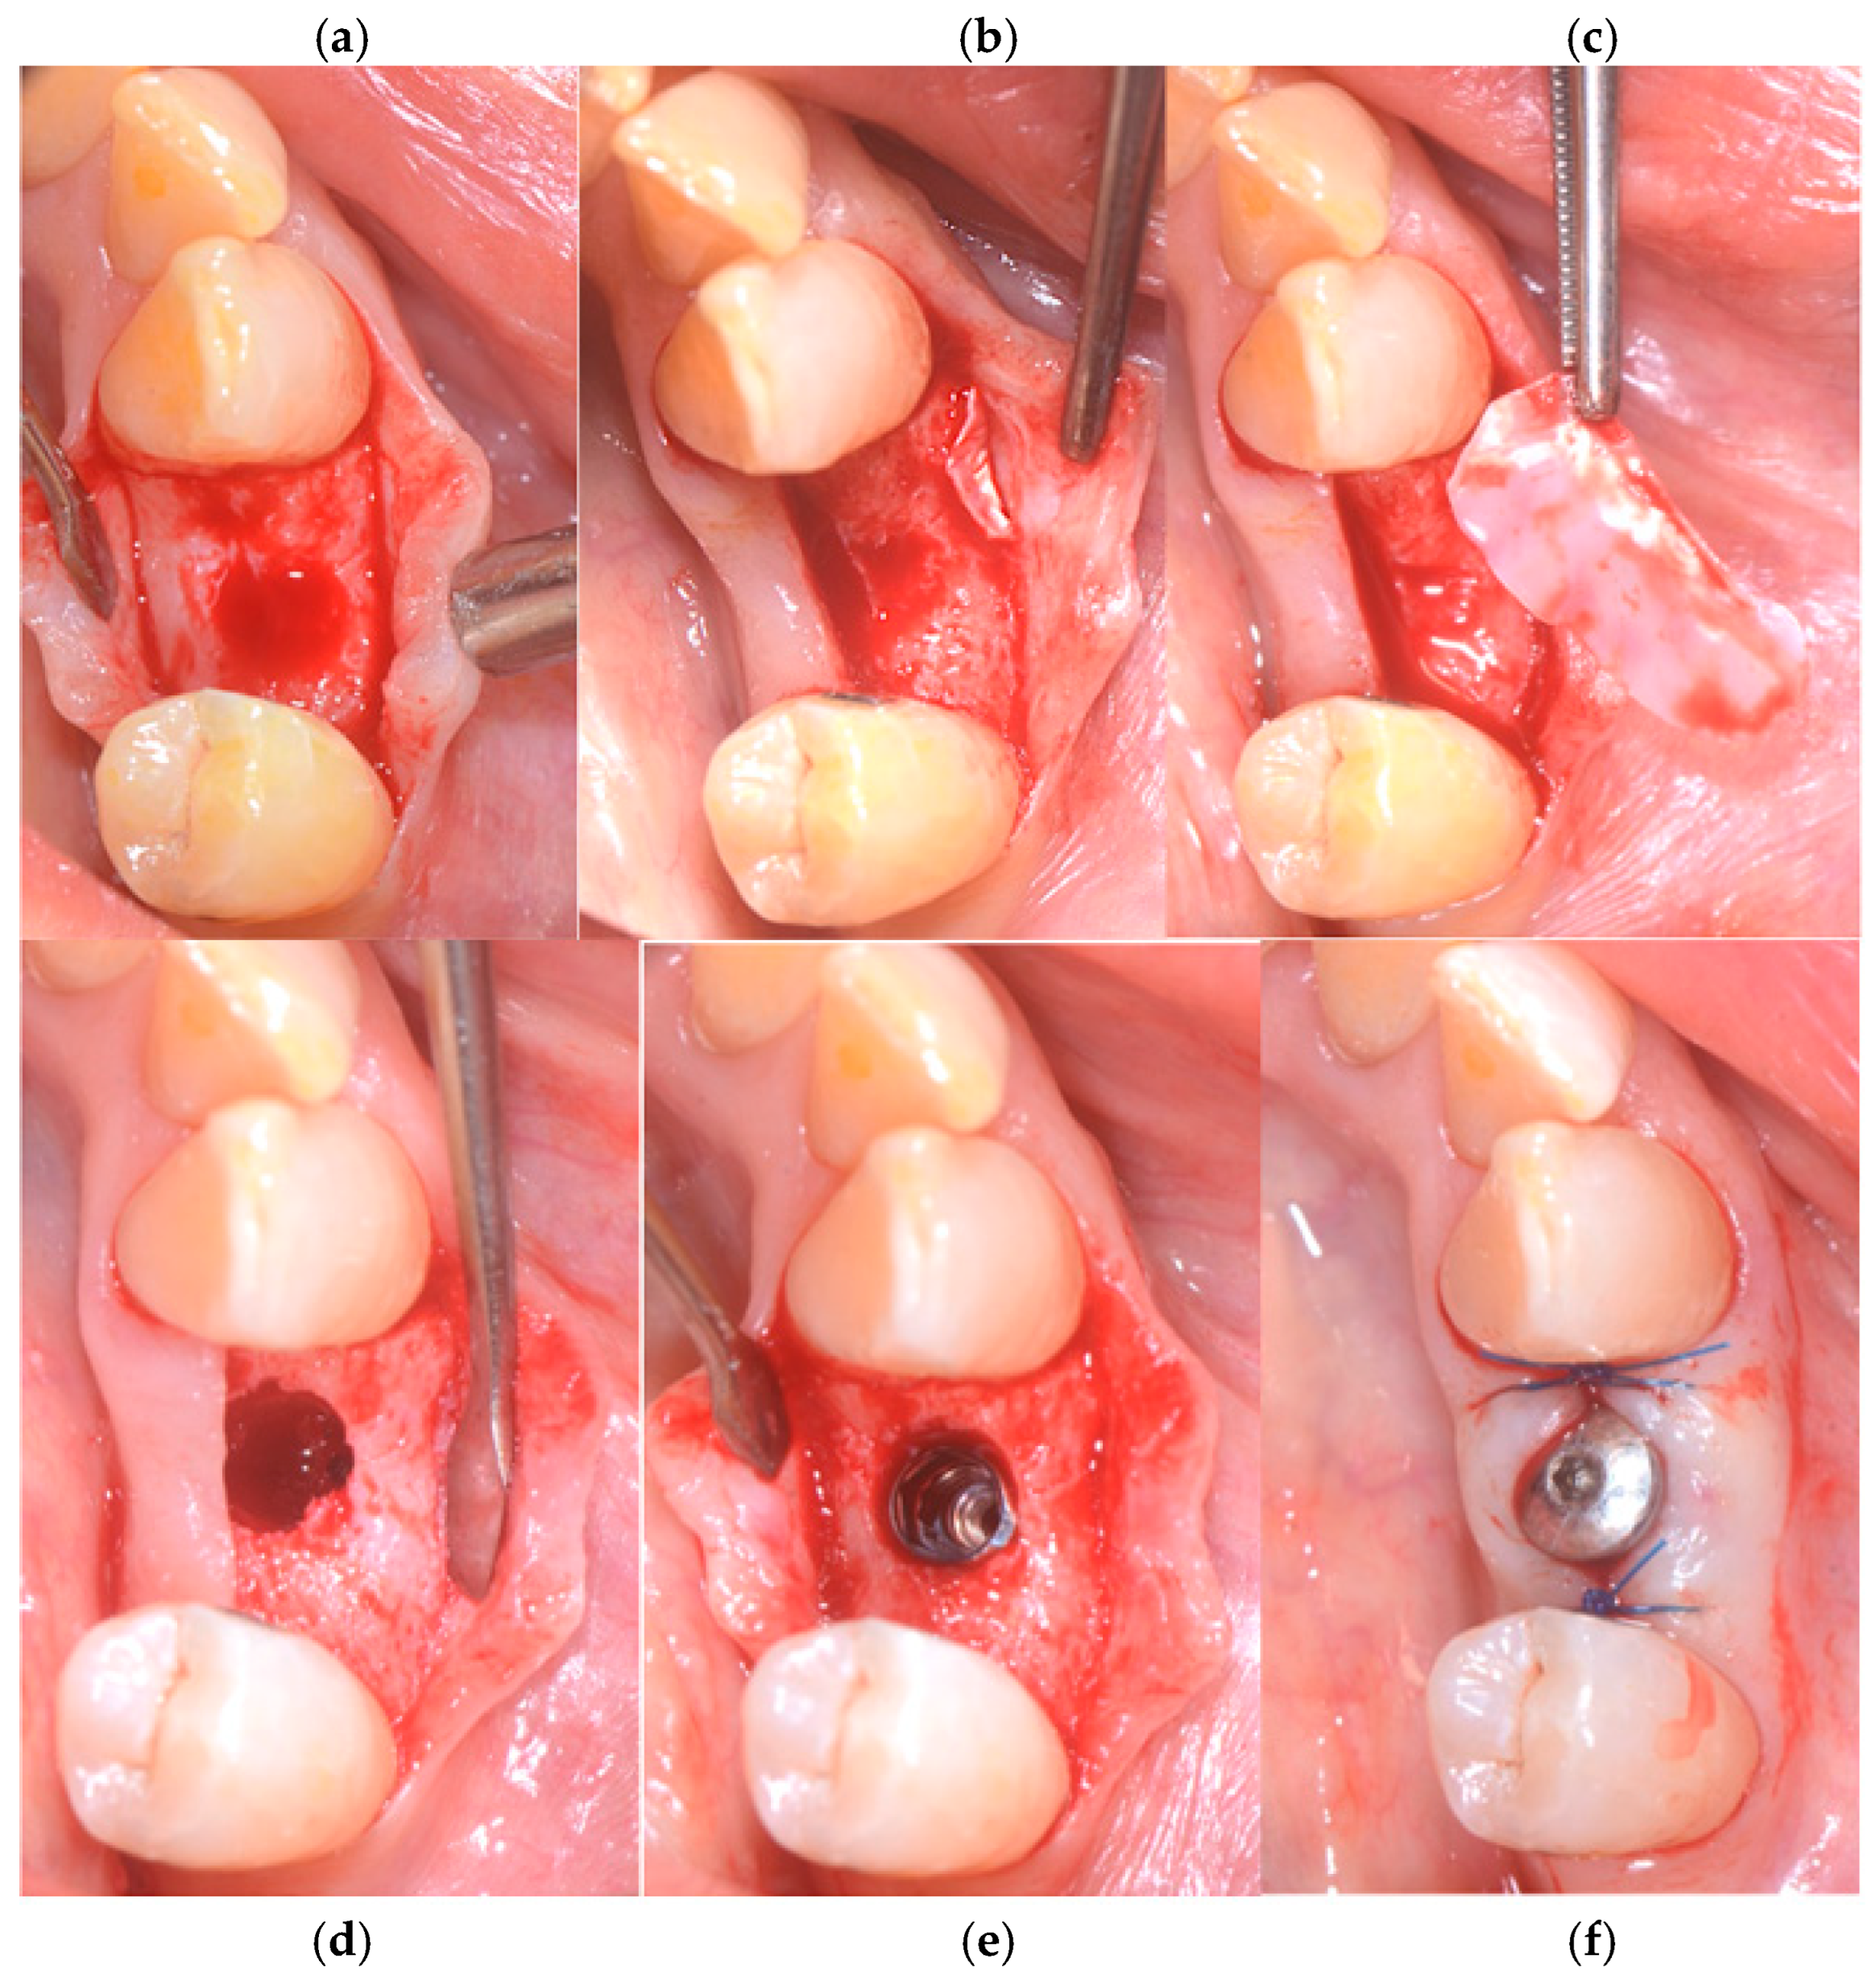

Subsequently, an incision of the papillae was made using a #15c surgical scalpel with a full-thickness envelope flap. A fenestration was observed on the buccal bone, the lingual–buccal length was approx. 8.3 mm.

A ptfe membrane, OSSEOGUARD of Zimmer Biomet (Warsaw, IN, USA), was placed between the mucosa and the fenestration site. To achieve haemostasis, 1 cubic centimeter of SPONGOSTAN™ (Ethicon, Somerville, MA, USA), a sterile gelatin sponge of porcine origin that is malleable, resorbable, and insoluble in water, with a whitish, porous appearance, was inserted into the socket. For suturing, a sling suture was applied to the papillae as well as a central cross, using a 5/0 PGCL absorbable suture from OMNIA (Fidenza, Italy). The sutures were removed after 7–8 days (Figure 2a–f).

Figure 2. (a) Preoperative sites, (b) alveolar socket, (c) fenestration in the vestibular bone, (d,e) ptfe OSSEOGUARD membrane from Zimmer Biomet in place, and (f) SPONGOSTAN and sling suture.